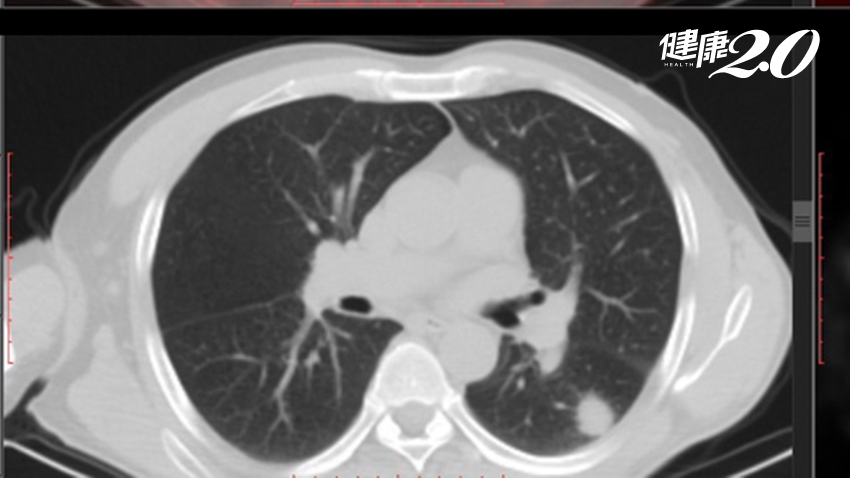

在臨床操作上,除病人症狀及家族史外,臨床醫師根據影像判讀,決定治療方向,除了大小之外,若病人影像學上呈現的多顆結節,是以毛玻璃狀陰影成分為主,那判斷是多發性肺癌的機率較高,會鼓勵病人早期接受手術治療診斷,最後以病理上的證據來分期及後續治療方針的安排。